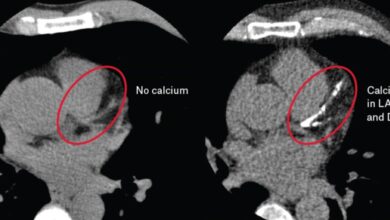

كشف استشاري أمراض القلب خالد النمر عن مفهومٍ خاطئ شائع، موضحًا عبر حسابه على منصة إكس أن الاعتقاد بأن ممارسة الرياضة تمنع الإصابة بأمراض القلب غير دقيق.

وأشار إلى أن الرياضة تقلّل من خطر الإصابة لكنها لا تلغيه تمامًا، خاصةً في حال وجود عوامل خطورة مثل التدخين أو ارتفاع الكوليسترول.